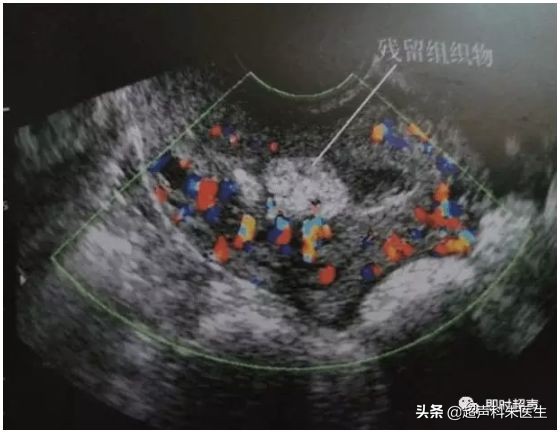

●药流或人流后,B超见宫腔内有不规则高回声或不均质低回声团,与正常肌层分界不清,夹杂宫腔无回声或低回声积血,彩超表现为绒毛着床部位有局灶性丰富的血流信号。

宫内妊娠物残留